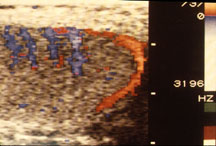

Color doppler ultrasound detects movement. Thus, it can detect flow of blood in organs. The image at the right shows normal blood flow in a testis (blue and red areas). Unfortunately, this is not the ultrasound of your patient.

This color doppler ultrasound shows no blood flow to the testis (there are not red and blue areas). You probably should have taken the patient directly to the operating room. Spermatic cord torsion is the most common diagnosis when boys present with an acute scrotum. Unless the testis is untwisted promptly it may be lost to ischemia.